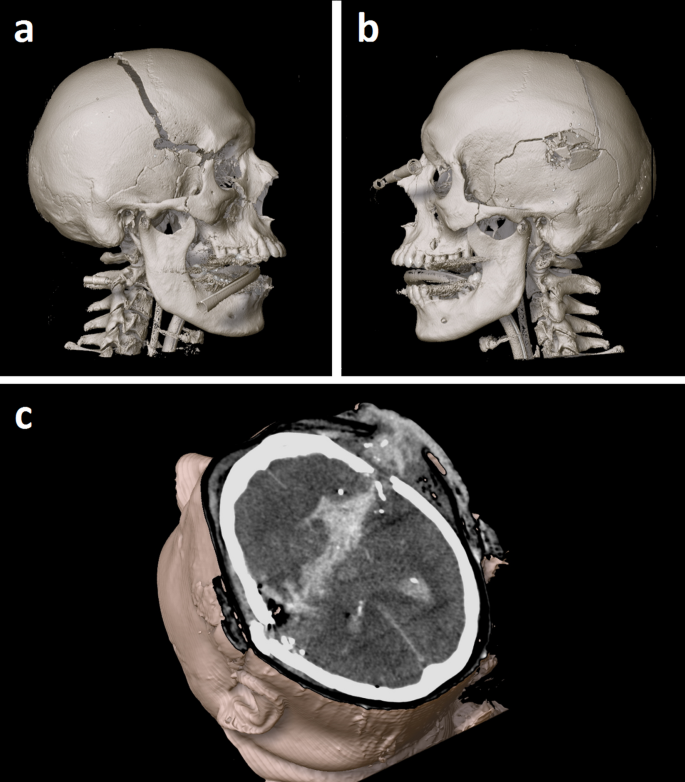

Self-inflicted injuries resulting from suicide attempts were observed in 81.0% patients in our cohort (see Fig. 3). The proportion of suicides resulting from head gunshot injuries is a complex issue influenced by multiple factors, including the overall homicide and suicide rate, prevalence of psychiatric disorders, firearm accessibility, and sociodemographic characteristics.

A 3D CT reconstruction demonstrating a typical penetrating craniocerebral gunshot injury sustained during a suicide attempt. (a) Entrance wound characterized by a small, circular defect in the right temporal region, accompanied by a displaced skull fracture. (b) Exit wound in the left temporoparietal region, surrounded by comminuted fractures with radiating fracture lines. (c) Axial CT slice showing the wound track of a 9 mm projectile crossing the midline, with extensive hemorrhage involving critical deep structures and extending into the occipital horns of the lateral ventricles. (We express our gratitude to the Editor-in-Chief of Czech and Slovak Neurology and Neurosurgery for kindly granting permission to include Fig. 3 in this manuscript, which was previously published in their journal58.

The proportion of suicides among firearm-related head injuries in countries with high firearm violence ranges from 3.3% to 48.8%5,12,13,20,23. Higher proportions of firearm-related suicides have been reported across Europe, particularly in Central European countries such as Germany (56.6%), Switzerland (64.7%), Austria (67.1–72.1%), and the Czech Republic (72.8%)14,24,25. This trend is primarily attributed to the notably low rates of firearm-related homicides in these countries, which results in suicides accounting for a larger proportion of firearm-related deaths11. The highest proportion reported in the literature to date is 79.7%, as observed in a Finnish study15. It is noteworthy that, during the period of this study, Finland faced a significantly high prevalence of suicide and depression26. However, in the years that followed, the suicide rate in Finland has seen a substantial decline, reflecting the impact of targeted mental health interventions and preventive measures27.